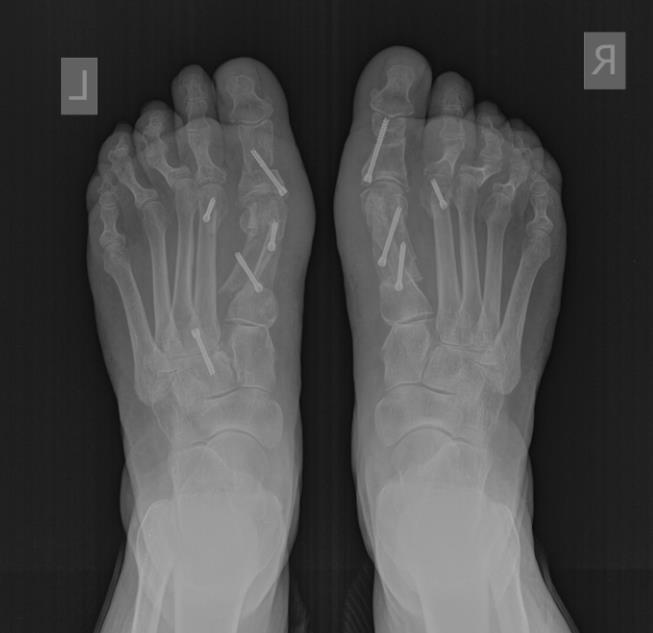

Рентген после операции Hallux valgus